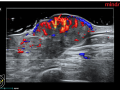

Progressão cutâneo do câncer de mama

Jul de 2024.

2.391

ultrassonografia mam...

doppler colorido